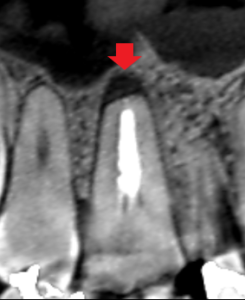

同じく上顎第一大臼歯の口蓋根の冠状断のCT画像です。

矢印の先に膿の影がみられます。

CTは、このように一つの根について角度を変えてみることができます。

この歯は、この歯にある全ての根に膿が確認できました。